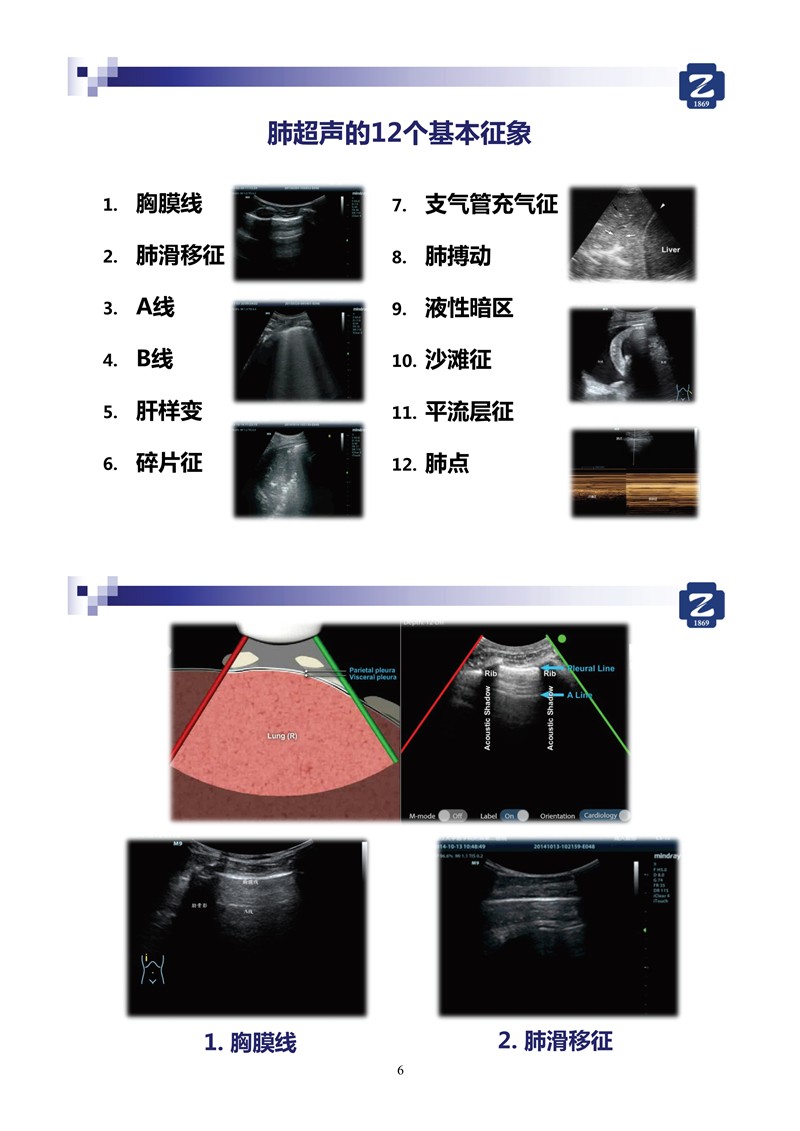

第二版新型冠狀病毒肺炎超聲診斷實用手冊_64.jpg